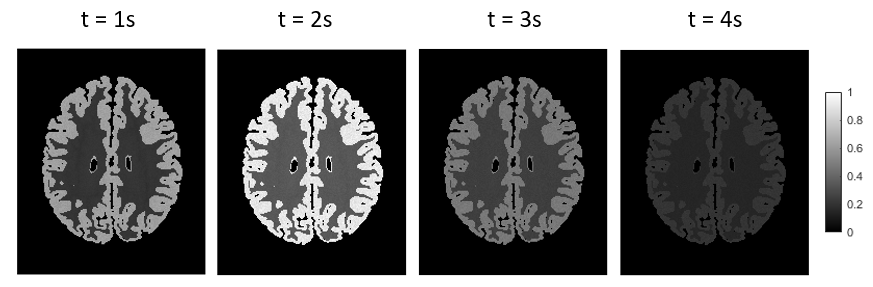

Figure 2 exhibits the simulated ASL image frames with the normalized concentration. The concentration first increases and then decreases with the increase of time.

Figure 2. The normalized simulated concentrations at four different time frames in the simulated microvascular network of the brain.